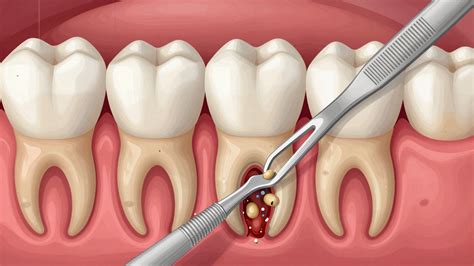

Chirurgické riešenie (kyretáž): Jednou z možností je čistenie maternice pri zákroku nazývanom kyretáž alebo revízia dutiny maternice. Tento zákrok sa vykonáva v celkovej anestézii a trvá približne 15 minút. Po zákroku žena väčšinou v ten istý deň odchádza domov. Komplikácie sú zriedkavé, ale môžu zahŕňať infekciu maternice či poranenie krčka maternice. Po zákroku sa obvykle objavuje slabšie krvácanie, ktoré by malo do týždňa ustúpiť. V prípade silného krvácania, silných bolestí alebo horúčky je nutné okamžite vyhľadať lekársku pomoc.

V prípade zamlčaného potratu je často nevyhnutná hospitalizácia, aby sa predišlo možným komplikáciám, ktoré by mohli ovplyvniť budúce tehotenstvá. Inštrumentálna revízia dutiny maternice je považovaná za najúčinnejšiu prevenciu komplikácií a zabezpečuje regeneráciu sliznice maternice.